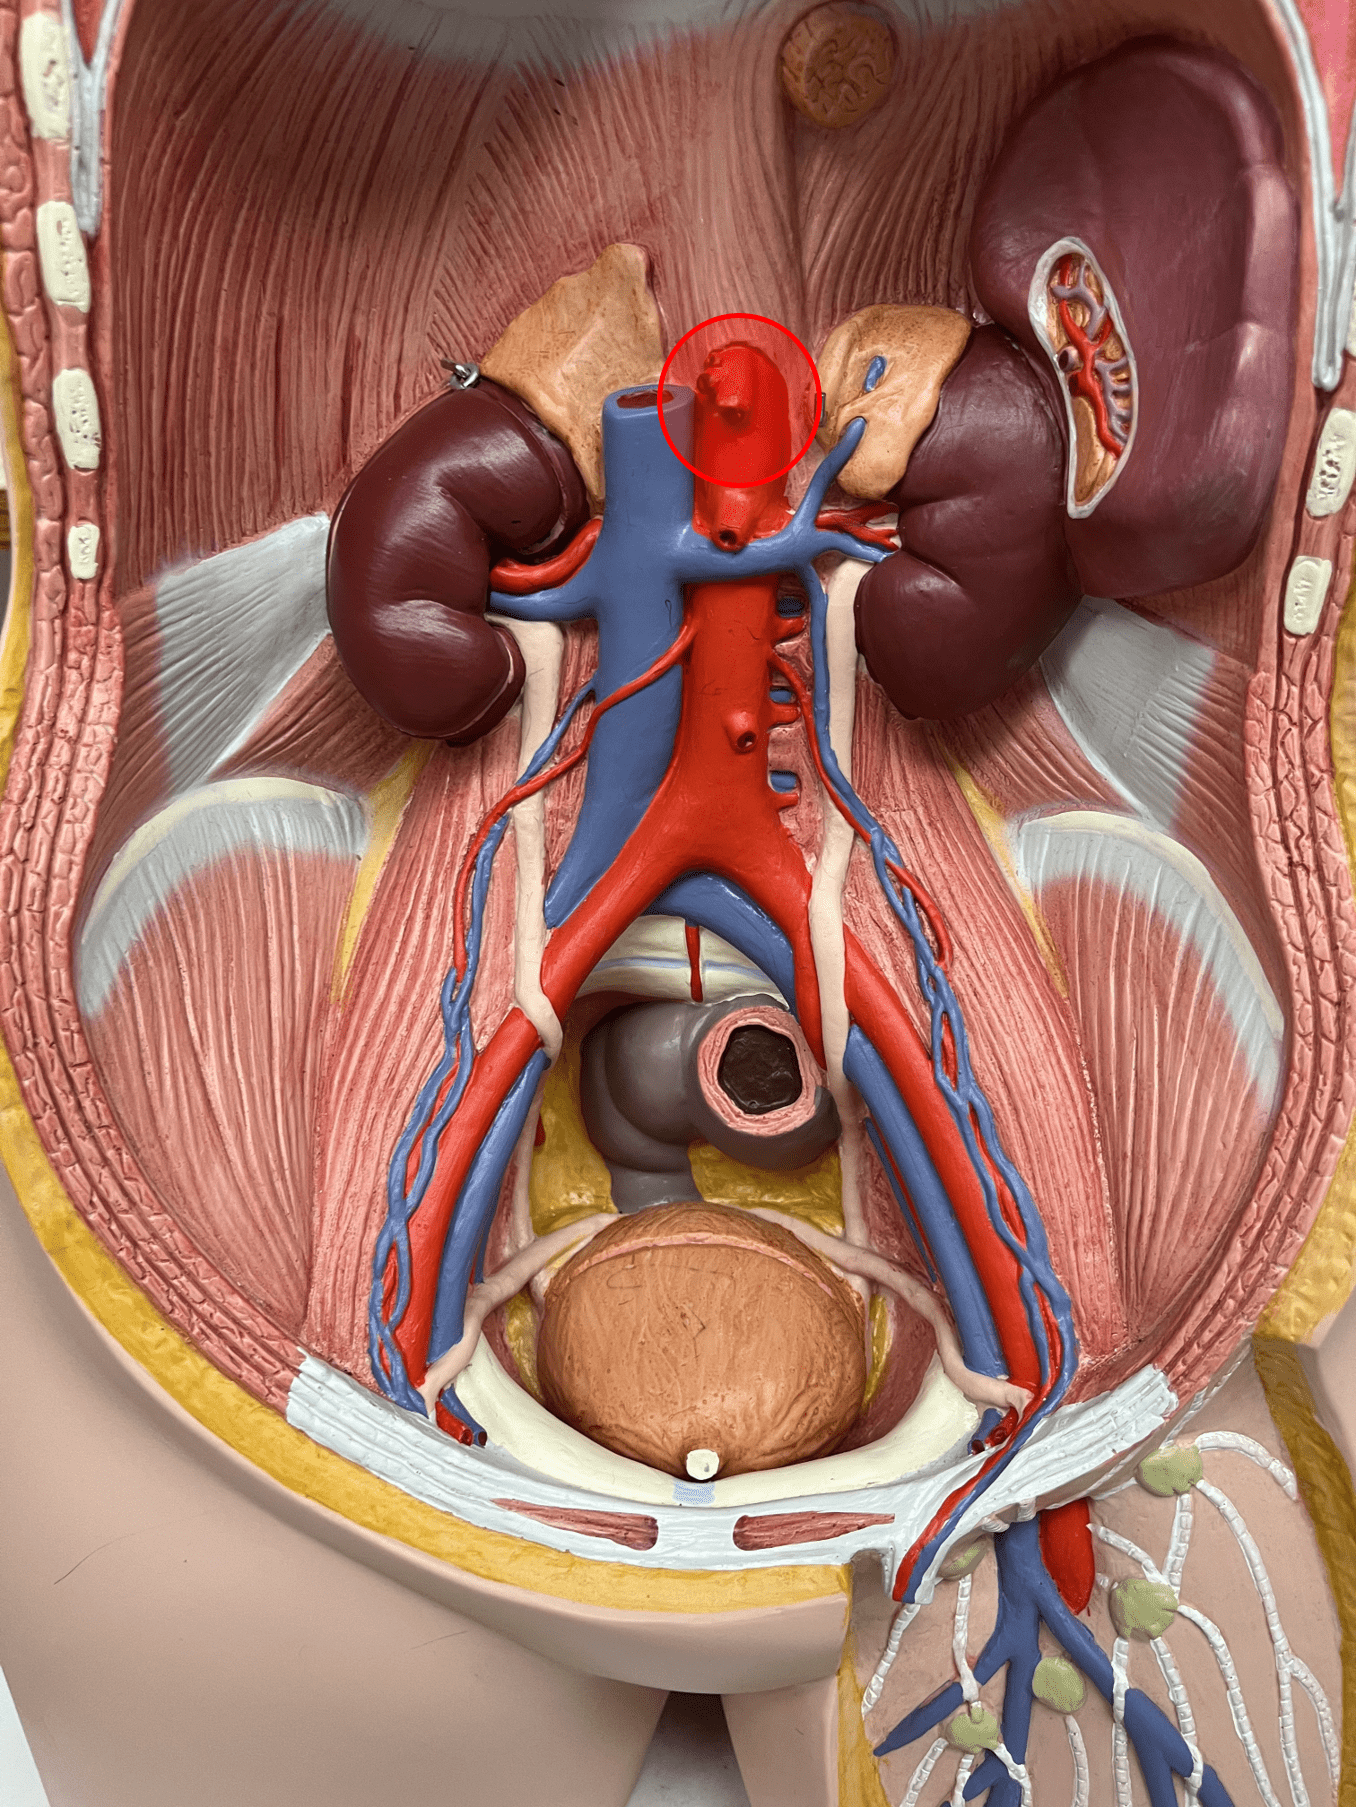

tunica externa

• Composed of loose connective tissue and collagen fibers.

• Also known as the tunica adventitia.

7

New cards

external elastic membrane

• A thin layer of elastic connective tissue.

• Found between the tunica externa and tunica media.

• Found between the tunica externa and tunica media.